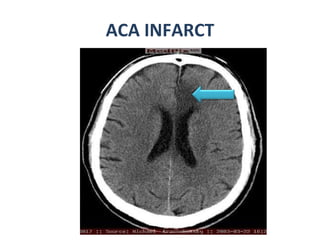

ACA INFARCT

Cerebral Arterial Territory MCA -most of  lateral hemisphere ,  Basal ganglia, insula,  ACA- Inferomedial basal ganglia,ventromedial frontal lobes,  anterior 2/3rd medial cerebral hemispheres , 1 cm supero medial brain convexity PCA -Thalami, midbrain,  posterior 1/3of medial hemisphere , occipital lobe,  postero medial temporal lobe